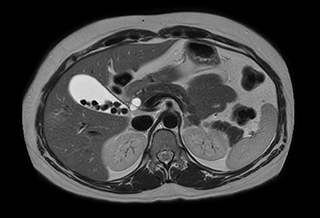

MRA run-off study with mDIXON

The subtractionless peripheral MR angiography shows improved vessel-to-background contrast and high resolution. Ingenia Ambition 1.5T.

Station

Ingenia Ambition

Pelvis

Voxels 1.3 x 1.3 x 3.2 mm, FOV 430 mm, 125 slices

Upper legs

Lower legs

Voxels 1.0 x 0.82 x 2.0 mm, FOV 430 mm, 125 slices